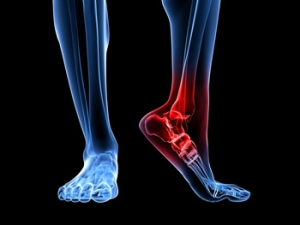

What Is a Peroneal Tendon Injury?

The peroneal tendons are bands of tissue that run behind the outer ankle bone. These tendons stabilize the foot and ankle and protect them from sprains. People who participate in sports, especially those involving repetitive ankle motion, and people with high arches are at an increased risk of experiencing a peroneal tendon injury. This type of injury can be caused by inflammation, tearing, degeneration or dislocation of one or both peroneal tendons. Injury to the tendons can cause symptoms such as pain, swelling, warmth, weakness, or instability in the affected foot and ankle. If you are experiencing foot or ankle pain, it is suggested that you consult with a podiatrist.

When the foot or ankle experiences trauma, a fracture may occur. Causes of foot and ankle fractures can vary; in some cases, an obvious impact to the foot or a fall can be behind a fracture. Alternatively, fractures can also occur because of increased stress on the bone over time. The location of the fracture can often give your podiatrist information on how the fracture occurred.

Pain, especially when bearing weight, is a telltale sign of a fracture. Limping due to this pain is a further sign of a foot or ankle fracture. Other symptoms include inflammation, bruising, deformity, and tenderness. A deformity may occur due to a shift in bone alignment or a joint dislocation near the fracture. While pain is a significant symptom of breakage, a patient who has nerve damage or who has diabetes may not feel this pain. In this instance, your podiatrist will look for additional signs to determine whether a fracture has occurred.

If you are experiencing severe pain, cannot walk without limping, have an open wound near the suspected break, or have numbness or tingling in the toes, you should see your podiatrist.